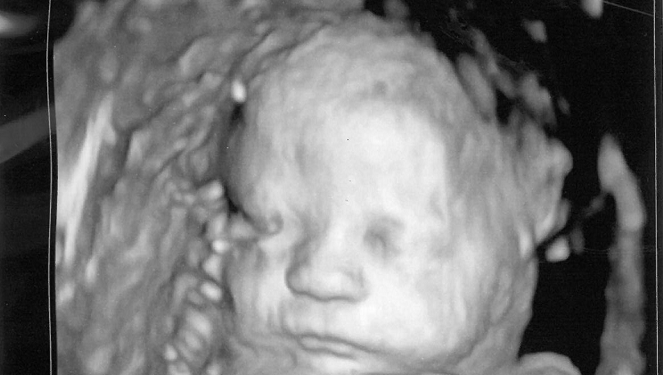

In addition, the sweeping Constitutional Amendment would end protections against brutal late-term abortions, upending our time-tested Pennsylvania law. The Amendment would mean abortion up to the moment of birth. Under current law, babies of six months’ gestation and older are protected from abortion, except in the rare cases where the life of the mother is at stake or the pregnancy would result in irreversible impairment of a major bodily function.